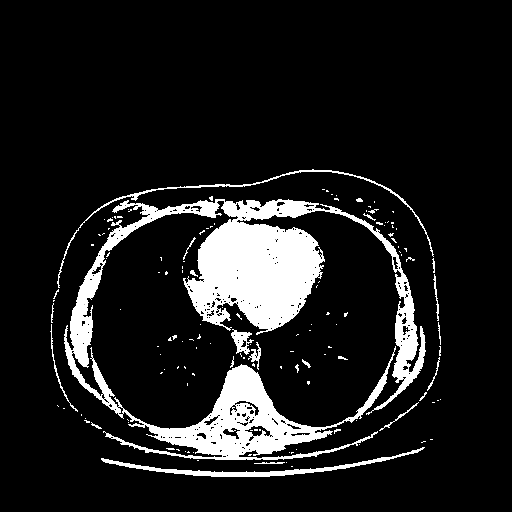

Original VENOUS CT scan

Full window (WL 1023.5, WW 4095 β†’ Low βˆ’1024, High +3071)

Actual HU range: [-1024.0, 3071.0]